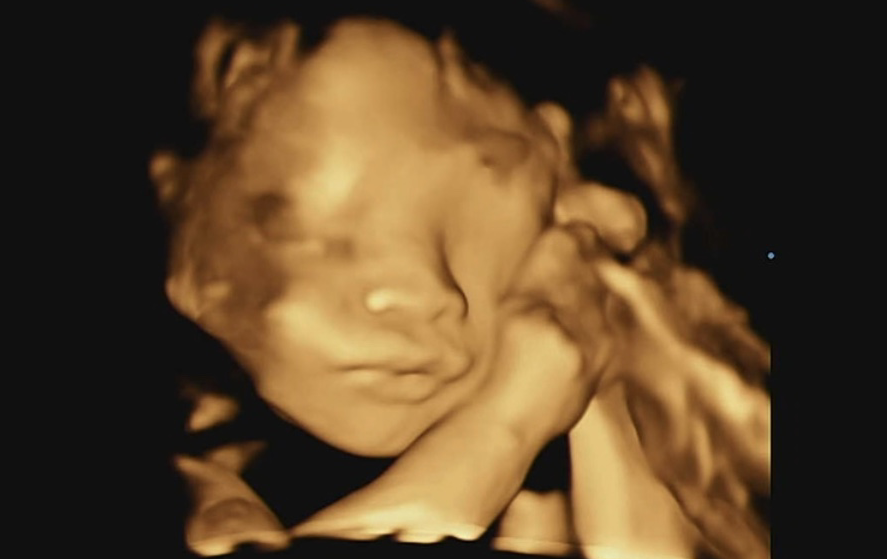

어느날 작은 생명체의 엄마가 되었습니다.